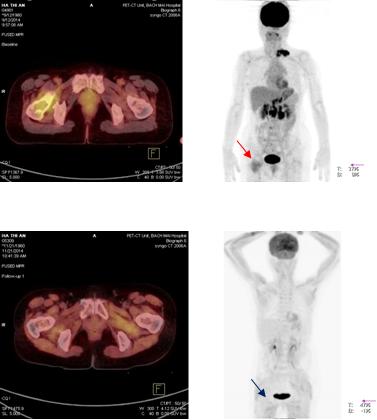

Trước điều trị: Hình ảnh hạch vùng thượng đòn trái trước điều trị (mũi tên đỏ)

Sau điều trị: Hình ảnh hạch vùng thượng đòn sau điều trị 3 chu kì hóa chất: hạch thượng đòn trái đã tan biến (mũi tên xanh: không còn tổn thương)

Hình 8: Hình ảnh so sánh trước và sau điều trị 3 chu kì hóa chất